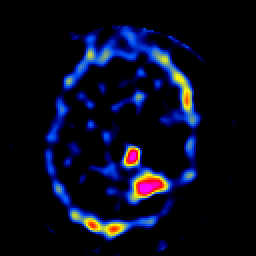

SPECT TL Study #8 -- Slice #40

[Home][Help][Clinical][Tour 1][Tour 2][Tour 3] Slice 40